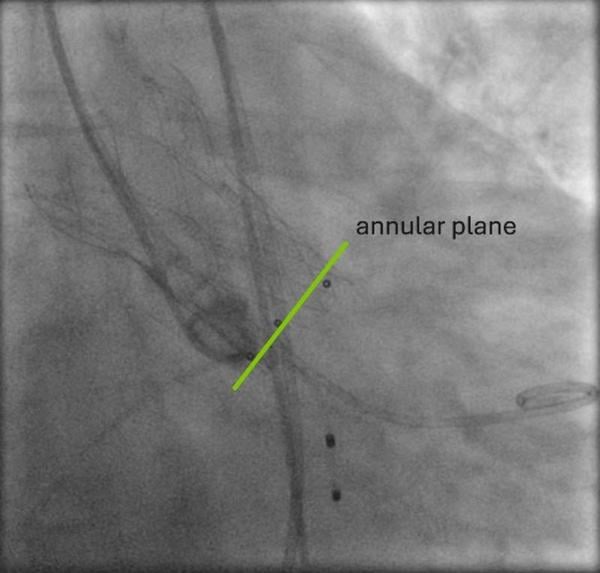

Die Planungs-Computertomographie (Abbildung 2-6) zeigte eine stark verkalkte Aortenklappe (Agatston-Score 3.398, Kalziumvolumen 2.627) mit leicht asymmetrischen Taschenklappen, wobei die nichtkoronare Tasche die größte war. Der linksventrikuläre Ausflusstrakt (LVOT) war verkalkt, beginnend auf Annulusebene bis 5,1 mm in den LVOT unterhalb der linkscoronaren Tasche reichend. Die Aortenwurzeldiameter waren niedrig: Anulus (aus dem Perimeter abgeleiteter Durchmesser 22,3 mm), linker ventrikulärer Ausflusstrakt (LVOT) bei 4 mm (19,9 mm), Sinus valsalva (SOV) (links 24,4 mm, rechts 25,3 mm, noncoronar 27,3 mm) und sinutubulärer Übergang (STJ) (24,0 mm). Darüber hinaus zeigte sich ein geringer Abstand des Ostiums der linken Koronararterie zum Annulus (8,6 mm) und eine horizontale Aorta (74°). Die Aorta, die Iliaca und die Femoralarterien waren für einen transfemoralen Zugang geeignet.

Abbildung 2: Computertomographie - Übersicht Aortenklappe

Abbildung 3: Computertomographie - Aortenklappe und LVOT